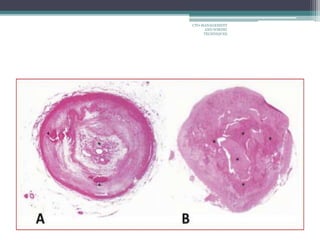

Histopathology

• Organized thrombus.

• Fibrotic plaque

• Calcified lesions.

• Proximal/ distal fibrous cap

• Micro channel in the occlusion segment

• #3 Some classifications,early chronic 1-3months,late chronic >3 months

• #6 Movat-Stained Sections Showing Temporal Changes in Vessel Size and Intraluminal Microvessels Representative histological sections of occlusions at 2(A),6(B),12(C), and 24 weeks (D). There was marked reduction in vessel size at 6 weeks (note the differ-ences in calibration). Microvessels (indicated by*) were maximal at 6 weeks with a decrease at the later time period.

• #7 The cross-sectional histopathological images of angiographically occluded coronary artery in the different occluded period.(A) 1.5-year chronic total occlusion that has organized thrombus with microchannel in original lumen area(*) with some calcification(arrowhead) in dense fibrous tissue. (B) 5-year chronic total occlusion in which much calcium(*) was observed without microchannels.